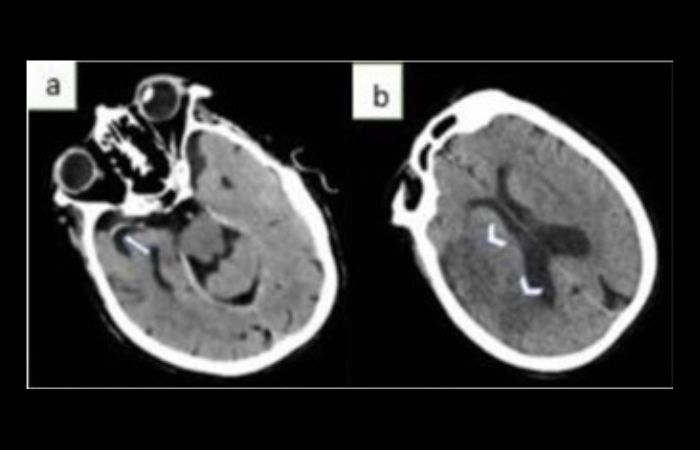

CT-Scan kepala gejala stroke iskemik (a) terlihat Hyperdense Middle Cerebral Artery Sign( HMCAS)di sebelah kanan (tanda panah) (b) Hipoatenuasi parenkim (kepala panah) terjadi setelah satu hari onset.

Stroke iskemik dapat terdeteksi melalui modalitas CT-Scan, salah satu tandanya adalah adanya Hyperdense Artery Sign (HAS) yang terlihat pada CT-Scan kepala.

HAS dianggap sebagai indikasi adanya thrombus di dalam lumen arteri, yang ditunjukkan oleh kepadatan yang lebih tinggi dibandingkan arteri normal, dan biasanya terdeteksi pada Middle Cerebral Artery (MCA) sebelum terlihat hipoatenuasi pada parenkim otak. Pada CT-Scan kepala, tanda hipoatenuasi parenkim dan HAS merupakan indikasi dari stroke iskemik.